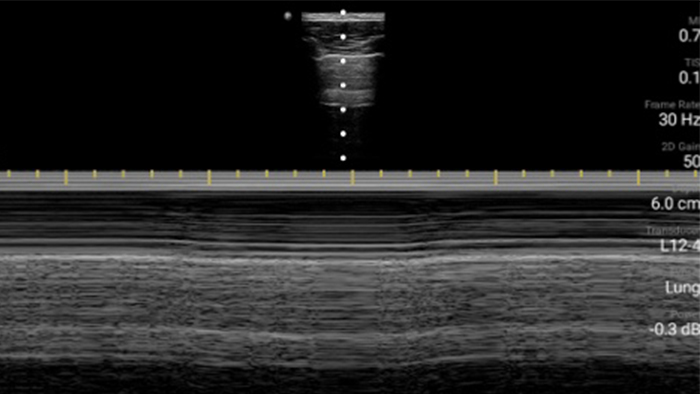

Lumify handheld ultrasound offers images that enhance diagnostic confidence.

See more when it counts

Lumify can help you make real-time decisions with more confidence, from assessment to recovery. Reveal the subtle details of an image, uncover enriched tissue definition with multiple angles and much more.